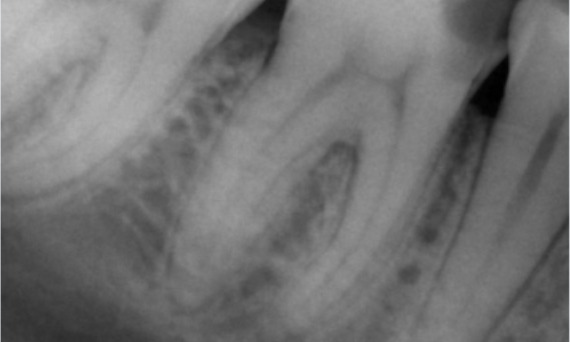

Avant : L’examen a révélé une lésion carieuse liée à la première molaire mandibulaire droite. L’examen radiographique a révélé la proximité de la lésion avec la corne pulpaire et, en l’associant à la plainte principale, un diagnostic final de pulpite chronique irréversible a été posé.

Après : La cavité d’accès a été réalisée de la manière la plus conservatrice possible. TruNatomy a été le système de choix en raison de l’âge du jeune patient. Nous devions préserver la dentine autant que possible afin d’augmenter la capacité de la dent à surmonter la charge occlusale et d’accroître la longévité de la restauration finale.